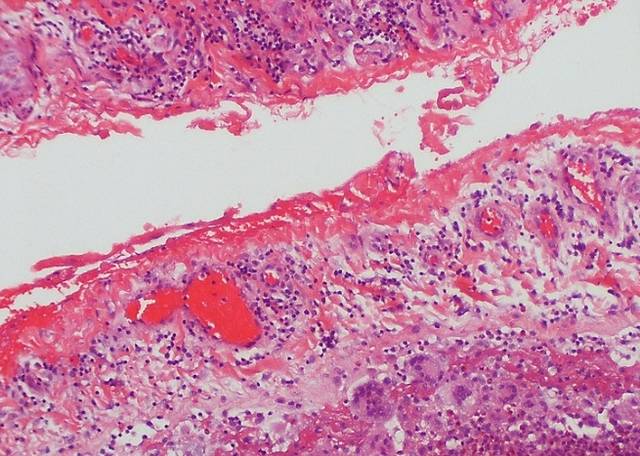

염증(炎症)은 유해한 자극이나 물질에 대한 생체반응 가운데 하나로 면역세포‧혈관‧점막세포 등이 관여하는 보호기전이다. 한 예로 우리 몸에 세균이 침입하면 대식세포 같은 면역세포가 즉각 출동해 염증유발물질을 분비해 침입자를 공격하고 다른 면역세포를 불러 모은다. 이때 주변조직의 혈류를 증가시키고 혈관의 투과성이 높아져 손상을 입은 부위가 벌겋게 부어오르고 열과 통증이 동반된다. 이것을 염증반응이라 부른다. 염증반응의 목적은 세포 손상을 초기단계에서 억제하고, 상처부분의 파괴된 조직과 괴사된 세포를 제거하며, 동시에 조직을 재생하는 것이다.

그러나 외부에서 침입한 세균이나 유해한 자극이 없는 상태에서도 면역세포가 지속적으로 활동하며 사이토카인 같은 강력한 염증유발물질을 끊임없이 생성할 때가 있다. 바로 만성염증이다.

이덕철 연세대학교 의대 가정의학과 교수는 “만성염증으로 생성된 염증유발물질은 매우 낮은 농도라서 세균이나 바이러스가 침입해 발생하는 급성염증과 같은 열이나 통증은 발생하지 않는다”며 “그러나 체내 혈액을 타고 전신으로 퍼져 나가 우리 신체의 여러 장기와 조직에 염증을 일으키고 손상시키며 몸의 에너지를 끊임없이 사용하기 때문에 만성적인 피로증상이 나타난다”고 설명했다.